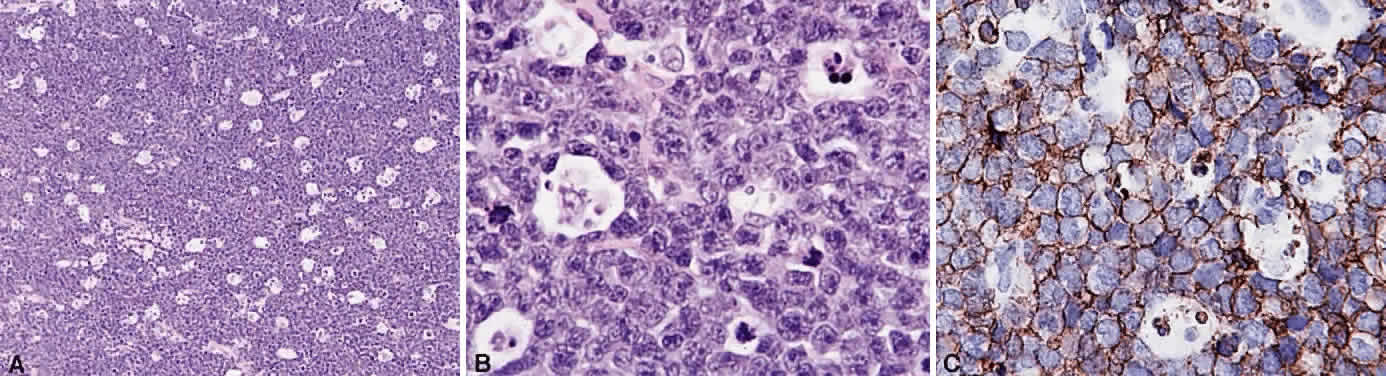

Numerous attempts have been made to classify lymphoid processes for clinical management and prediction of prognosis. Early classifications included only disease localized to the lymph node, which made classification of extranodal disease difficult and inaccurate. The Rappaport classification, first developed in 1956 and then modified in 1978, attempted to categorize lymphomas in two ways, first, using cytologic characteristics identified by conventional stains, and second, distinguishing between the follicular and diffuse growth pattern histologically38,39 (Table 3). The distinction of nodular, or follicular, and diffuse growth was considered useful because of the generally indolent nature of follicular growth, in which the tumor cell aggregates resemble germinal centers and disrupt the normal architecture of the node, compared with the appearance of diffuse growth, in which the lymph node is completely obliterated by a dense monotonous sheet of lymphocytes. In subsequent years, however, it was found that the descriptive growth pattern and cytogenetic characteristics of the Rappaport system did not predict prognosis reliably and were biologically inaccurate. The complexity of correlating degrees of differentiation, mitotic activity, and cytologic characteristics to prognosis have made lymphomas difficult to classify and have led to subsequent systems. The second system, proposed by Lukes-Collins in 1974, classifies lymphoma histologically according to its normal counterpart B-cell, T-cell, or null cell origin40,41 (see Table 3). Histologically, cells may appear small cleaved, large cleaved, small noncleaved, or large noncleaved, depending on the stage of B-cell arrest during normal transformation to immunoblast. Ninety percent of lymphomas are of B-cell origin, and the null cell also usually is of B-cell origin, although 10% may originate from T cells or histiocytes.42,43 Burkitt's lymphoma, the only lymphoma common in children, is a B-cell variant with a background of reactive histiocytes. As a result of histologic classification by Lukes-Collins, 76% of histiocytic lymphomas according to the Rappaport system were found to be not of histiocytic origin but of lymphocytic origin.40,44 The third system, the Working Formulation devised by the National Cancer Institute in 1982, attempted to predict prognosis by grouping lymphoma according to natural history, response to therapy, and overall survival.45 Three broad categories were established in terms of 5-year survival rates, the low-grade with a 50% to 70% survival rate, intermediate with 35% to 45%, and high grade with 23% to 32% (see Table 3). Orbital reactive hyperplasia, a relatively low-grade lesion, can be associated with systemic disease, whereas malignant or high-grade orbital lymphomas may be isolated findings. The Ann Arbor Staging Classification for Hodgkin's and non-Hodgkin's lymphomas was developed to stage disease based on systemic areas of involvement as a means of establishing a baseline for treating disease and following clinical progression46 (Table 4). Histologic classification, however, has been recognized as more useful than localization in the clinical management of nonHodgkin's lymphoma.47

While the Lukes-Collins and Working Formulation classifications were in wide use in the United States, the European literature made references to the Kiel and updated Kiel classifications, which led to disparities in classifying lymphoma. Another classification proposed by Jakobiec and coworkers was the most comprehensive classification available for orbital disease but failed to integrate systemic lymphoma, which is known to be associated in approximately half of cases.1 The most recent classification has made the system universal, comprehensive, and useful to interdisciplinary teams that characteristically manage patients with lymphoma. The International Lymphoma Study Group in 1994 developed the Revised European-American Lymphoma (REAL) classification (Table 5), which classifies lymphoid disease by the cell of origin into B-cell, T-cell, and natural killer cell lymphomas, leukemias, myeloma, and variants of Hodgkin's disease26 (Fig. 4). The identification of the putative benign progenitor cells has been inferred through the use of cell marker studies. The results of molecular genetic studies to identify immunoglobulin gene rearrangements and cytogenetic studies to detect chromosomal translocations in monoclonal proliferations have also been incorporated. A significant contribution of the REAL classification has been to incorporate primary extranodal lymphomas as recognizable and classifiable entities. As a result, new variants in this list include lymphoplasmacytic lymphoma, mantle cell lymphoma, marginal zone B-cell lymphoma, particularly mucosal-associated lymphoid tissue (MALT) lymphoma, subclasses of large cell lymphoma, and the natural killer cell lymphomas. Comparisons of the REAL classification to the Working Formulation and the Kiel classification are shown in Tables 6 and 7, respectively.48 The first series of 112 orbital lymphomas using the REAL classification reported the accuracy and utility of the system in classifying orbital lesions and predicting prognosis in combination with currently available immunophenotyping and immunocytogenetic studies.49 The REAL classification does not classify disease based on the degree of differentiation or clinical prognosis. However, a proposed prognostic scheme has been developed in accordance with the REAL classification28 (Table 8). In this text, tumor nomenclature adheres as strictly as possible to the REAL classification.